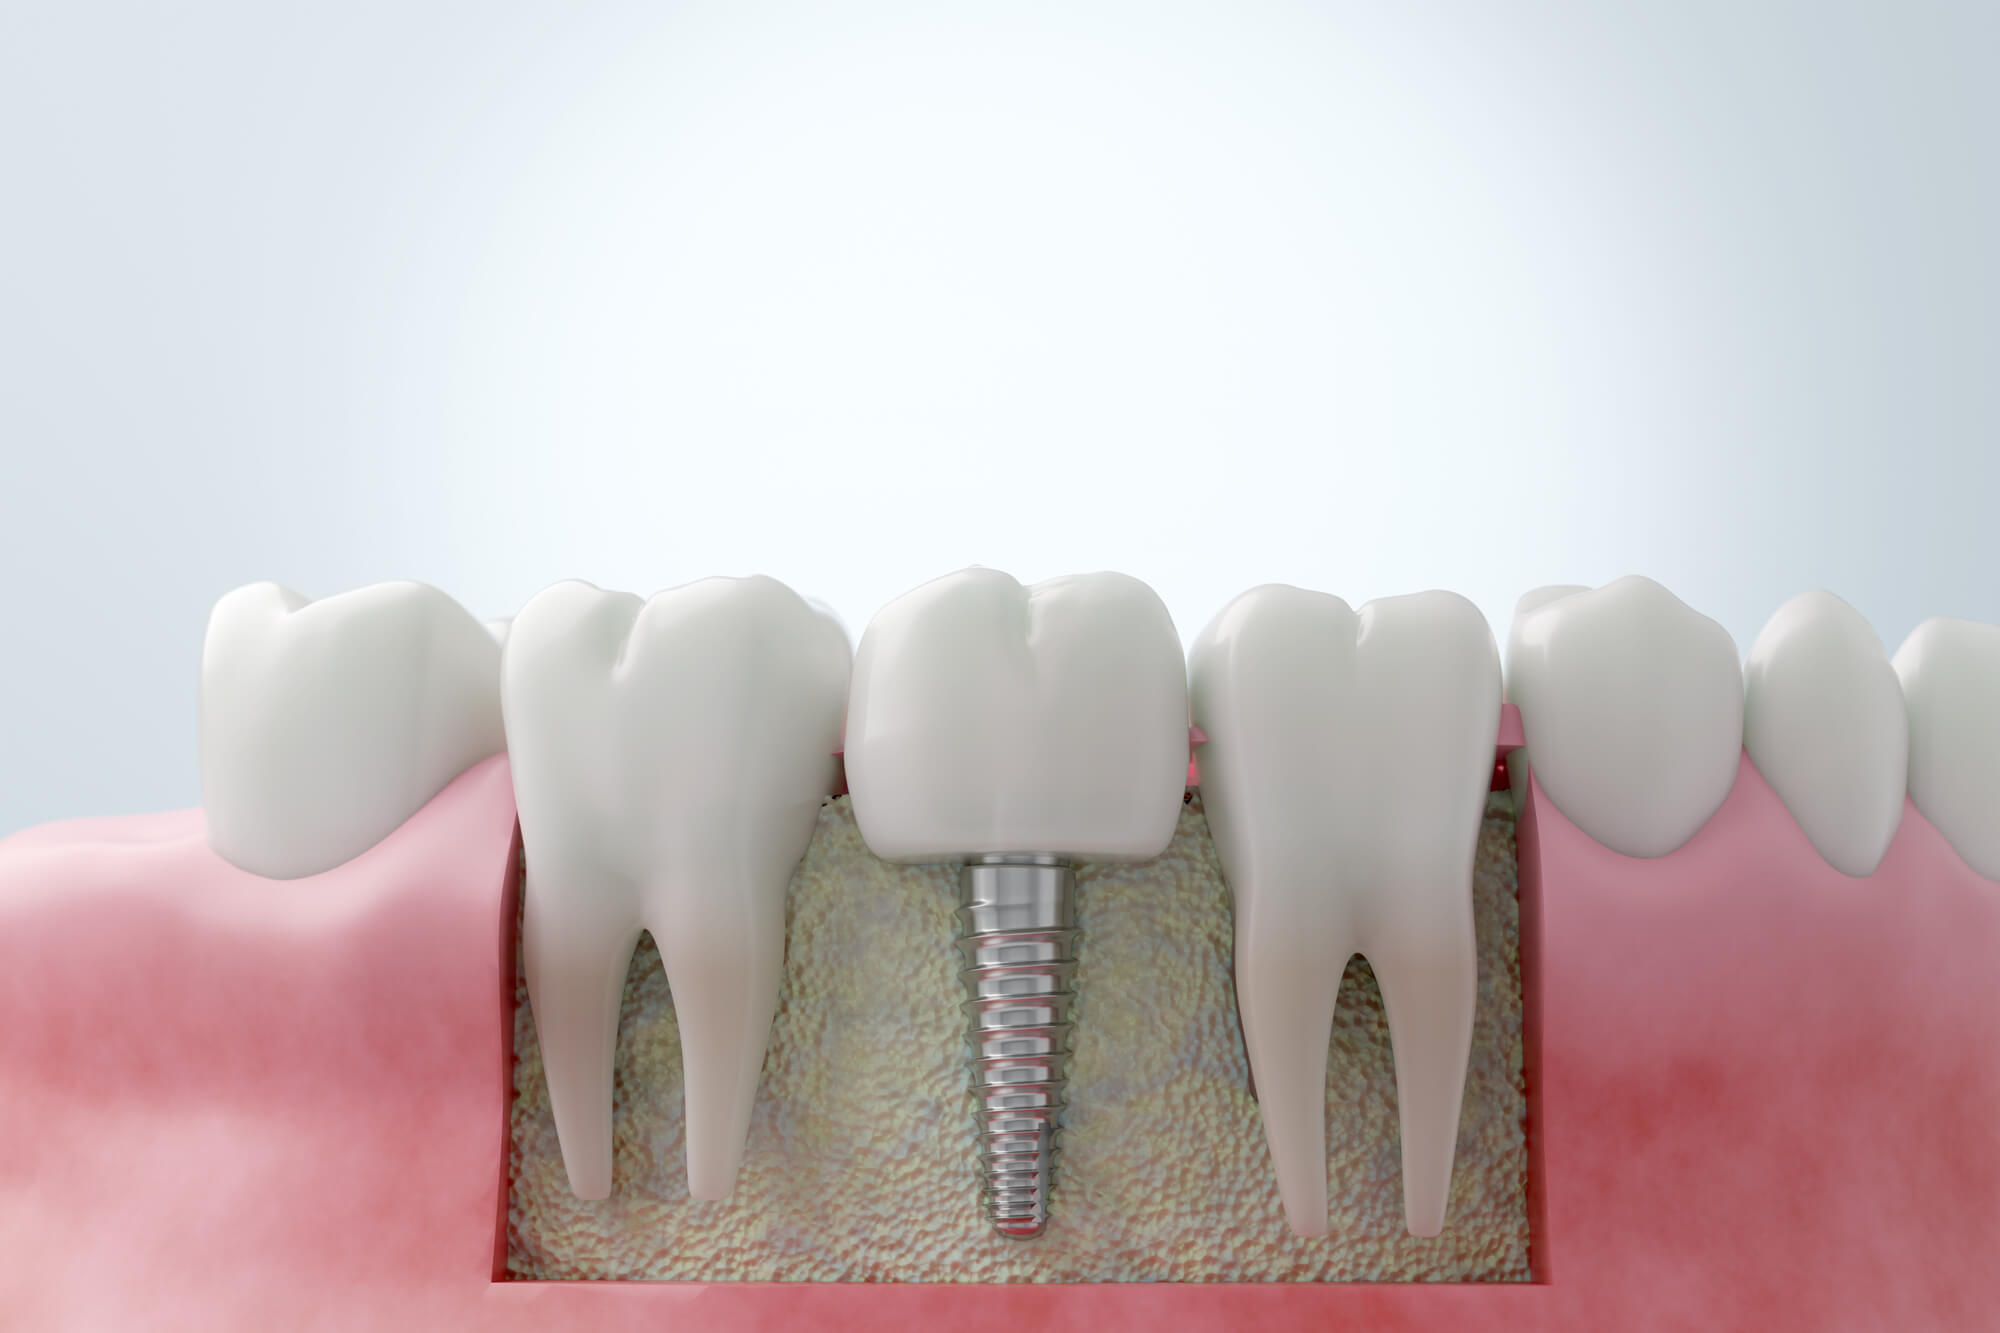

GBR(骨再生誘導法)とは、インプラントを埋め込む箇所の顎の骨の厚みや高さが十分でない場合に用いられる治療法です。単に骨を増やすというよりも、骨の再生を促進させ、新たな骨の形成を導くというのが特徴です。

治療方法としては、治療箇所に「自家骨(自分の体から採取した骨)」あるいは、「人工の骨補填材」を使用し、メンブレンと呼ばれる人工膜でその部位を覆い、骨が再生されるのを待ちます。

特に、歯槽骨が痩せてしまったり、抜歯した後に骨の吸収が進んでしまったケースでは、GBRが有効と言えるでしょう。このGBRにより、骨が薄い・少ない方でもインプラント治療を受けることができるようになります。

②インプラントを埋め込む

まず、歯茎を切開し、顎の骨にドリルで穴を開けて、インプラントを埋入します。

しかし、GBRが必要な患者様の場合、骨の量が十分でないことが多く、インプラントが完全に骨に収まりきらず、一部が飛び出る状態となります。

③自家骨または人工の骨補填材を充填する

インプラントを埋入した後、骨の形成をサポートするために、自家骨または人工の骨補填材を使用します。これらをメンブレンと呼ばれる人工膜で覆い、骨再生を妨げる線維芽細胞の侵入を防がなければなりません。